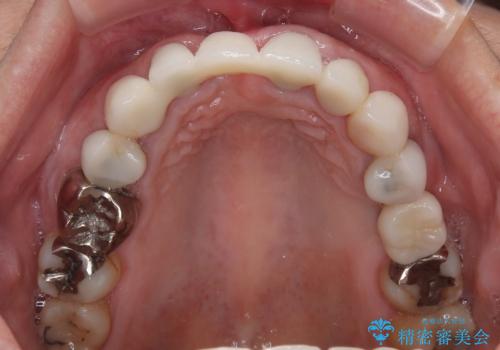

- 前歯が土台ごと外れてしまうとのことで来院された患者様です。

問題の歯は、歯根まで破折している状態で、抜歯が必要と判断されました。

周辺の歯は20年以上前に装着したクラウンで、色合いや形態が気になっているとのことで、オールセラミックブリッジにて補綴治療を行うこととしました。

ところが、土台となる歯は、十分な維持力が得られないほど歯ぐきの中に埋もれており、歯ぐきも腫れやすい状況でした。

まずは土台の歯を引っぱり出し、外科処置により歯肉の状態を十分に整えた上で、オールセラミッククラウンにて補綴することとしました。

元々の土台は歯肉の中に埋もれており、歯肉が著しく腫れている状態だったため、歯を引っぱり出すこととしました。引っぱる期間は2ヶ月ほどで済み、その後歯周外科処置を行ったことで、土台周りの歯肉は腫脹のない健全な状態へと改善されました。